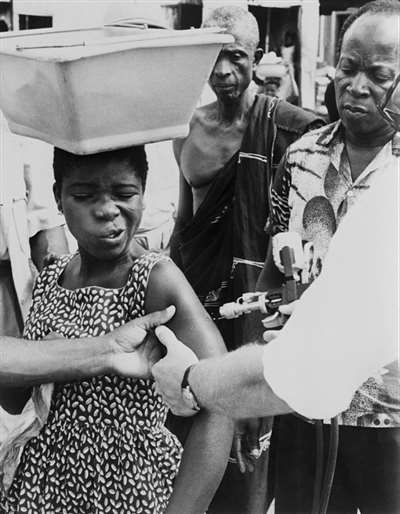

1969年,尼日利亚,当地居民接种天花疫苗。图|视觉中国